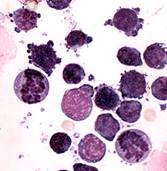

Fig.1. Aspectul histologic al aspiratului din limfonoduri, de la vaci cu limfosarcom. Se observa limfocite numeroase, cu o rata mare a raportului nucleu/ciroplasma si nuclei ovali cu cromatina fina. In fundal sunt prezenti nuclei goi, picaturi citoplasmatice si eritrocite (https://www.vet.uga.edu/vpp/clerk/collins/index.php).